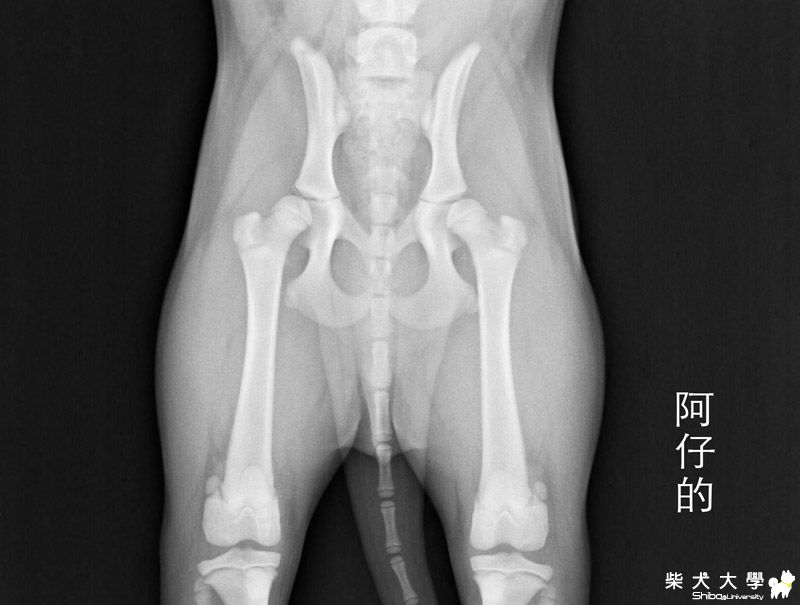

[相簿]阿仔。的缺憾(原發表者:朱元宏)

醫生原本懷疑是膝關節或踝關節的生長板有單邊停止的可能,而影響了姿勢,

於是,建議拍攝膝及踝的x光片,

拍攝的結果,膝和踝關節都正常,骨頭生長板也都正常,

但髖部的股骨頭和髖臼的密合度不佳,是鬆動的,包覆度不夠,角度也不夠,

但因為髖關節是要兩歲才能做判定的,

現在只能說是髖關節是有鬆動的現象,等六個月大後再追蹤,